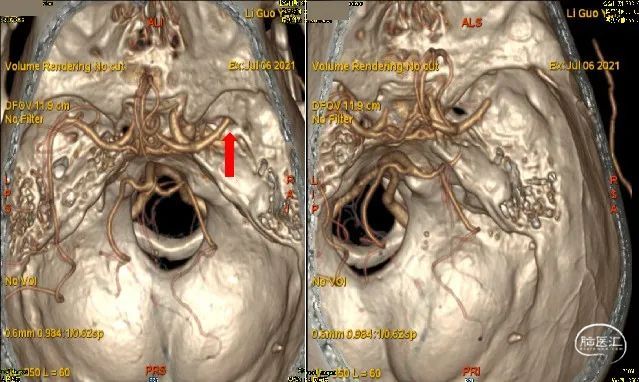

颅脑CTA:左侧颈内动脉闭塞、右侧大脑M1远端闭塞。

患者症状、体征考虑右侧M1为责任血管,左侧颈内慢闭可能性大,左侧M1通过前交通动脉代偿。

术前DSA

M1闭塞消失 溶栓后血栓移位?M2下干取栓?